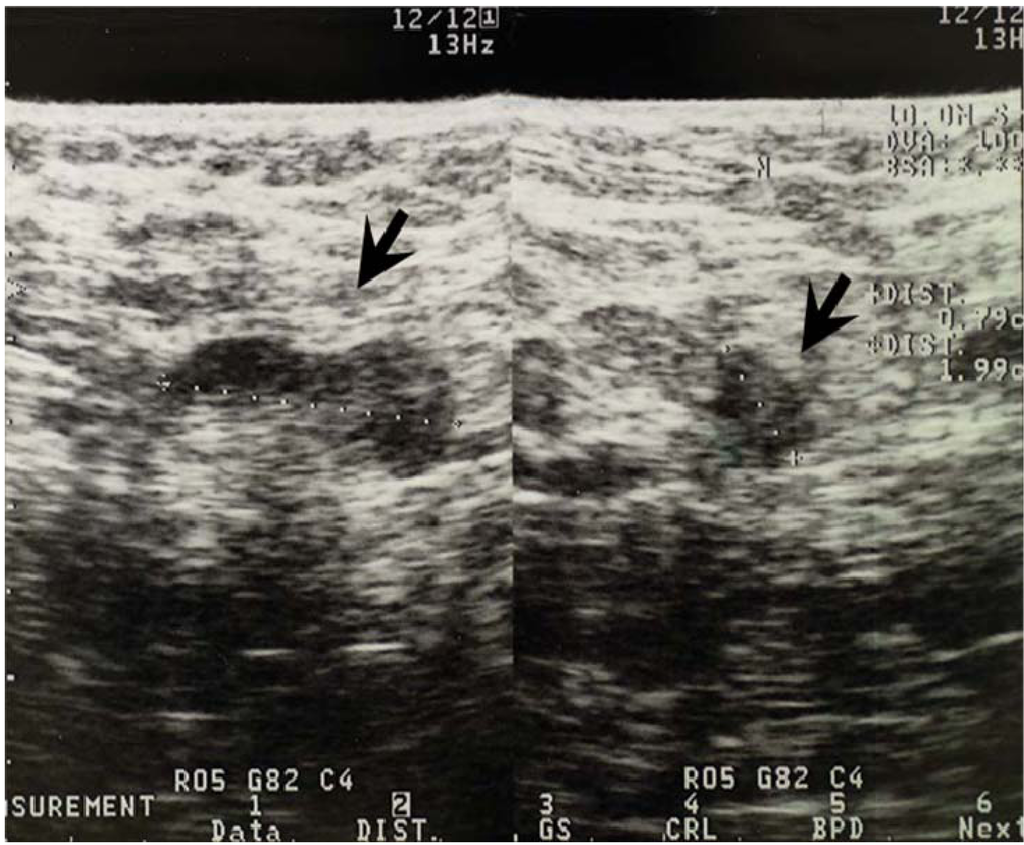

3.2. Ultrasonographic Examination and Criteria for Axillary node Evaluation